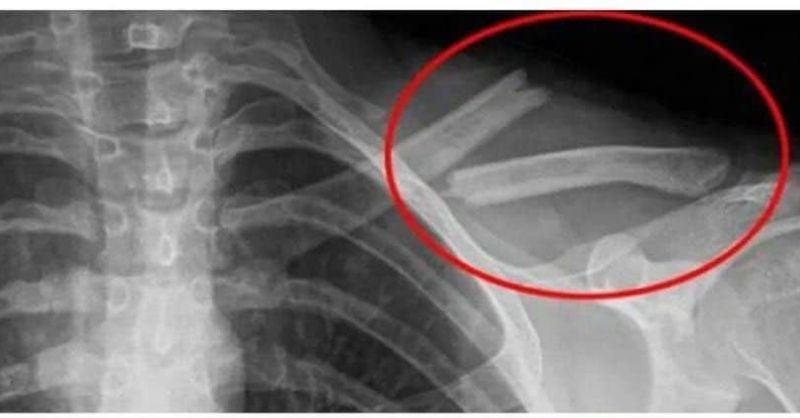

Eating these foods will reduce the amounts of calcium in the body, causing negative effects on bones and joints

Eating these foods regularly will cause calcium in the body to decrease, causing negative effects on bones and joints. 1. Salty Foods Delicacies such as pickles, ham, instant...

This poison destroys your bones, but you drink it every day!

Soda is a widely consumed beverage globally, but its frequent consumption can result in several health problems. From weight gain to negative effects on bone health, the high...